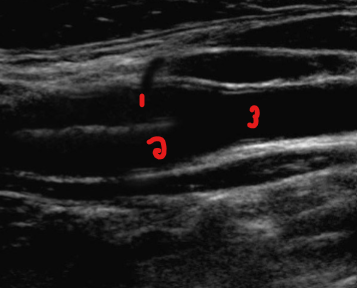

Label the structures on this image.

ICA

ECA

CCA